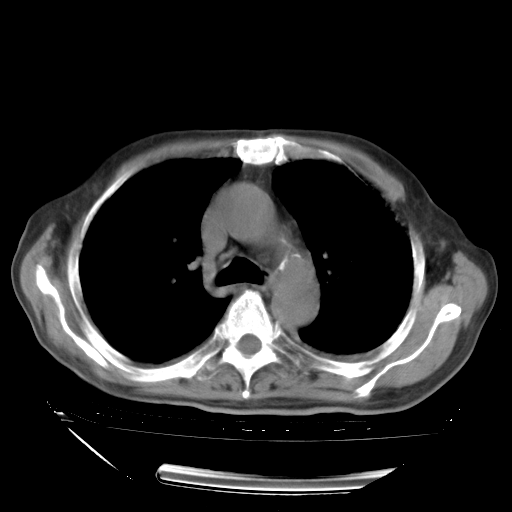

甲强龙80mg/日+抗结核治疗(异烟肼+利福霉素+乙胺丁醇)10天。复查肺部CT。

治疗10天肺部CT

今天带四次肺CT片到市医院,影像科4~5个主任都认为不考虑粟粒性肺结核。主要理由是在3月19日、4月2日、4月27日的CT片没有见到确切异常(肺结核)影像。影像科主任们建议找呼吸内科主任,呼吸内科主任认为首先考虑粟粒性肺结核。